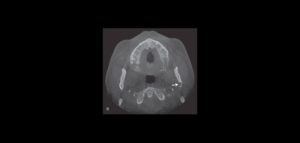

132 – Tratamiento de la reabsorción radicular interna idiopática perforante: controles radiográficos

La reabsorción radicular interna (RRI) es una afección inflamatoria que resulta en la destrucción progresiva de la dentina intra-radicular a lo largo de los tercios